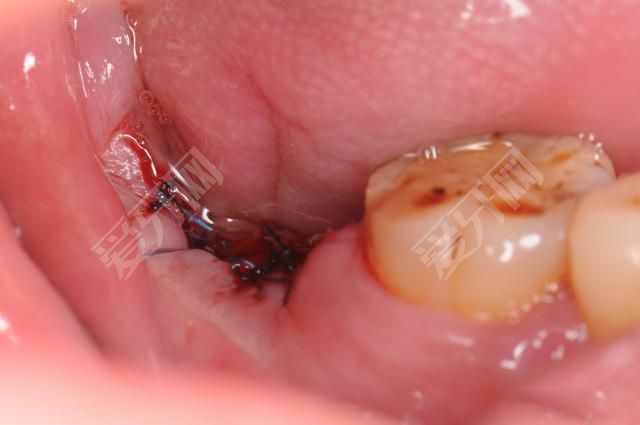

2.如果牙根損傷嚴(yán)重,需要拔掉損傷的牙根,甚至全部拔掉,然后植入人工牙根后再種植。

種植前是否拔牙取決于醫(yī)生檢查自己的牙齒狀況。種植手術(shù)往往對醫(yī)生的技術(shù)水平和要求非常嚴(yán)格。只有有經(jīng)驗豐富的醫(yī)生才能保證種植手術(shù)的順利進行。

種植牙是將種植體直接放入牙槽骨組織,需要通過種植體和牙槽骨組織的緊密融合來獲得固定和支撐。所以要等到種植牙傷口完全愈合后再去醫(yī)院洗牙。